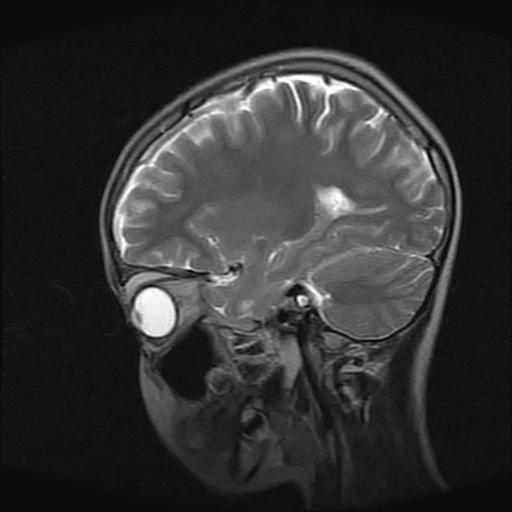

9岁女孩,三岁时诊断为癫痫,一直服丙戊酸钠,现患者一般情况良好,家长复查核磁片,看能否停药..

巨脑回

停药要结合临床,如无发作可以停。